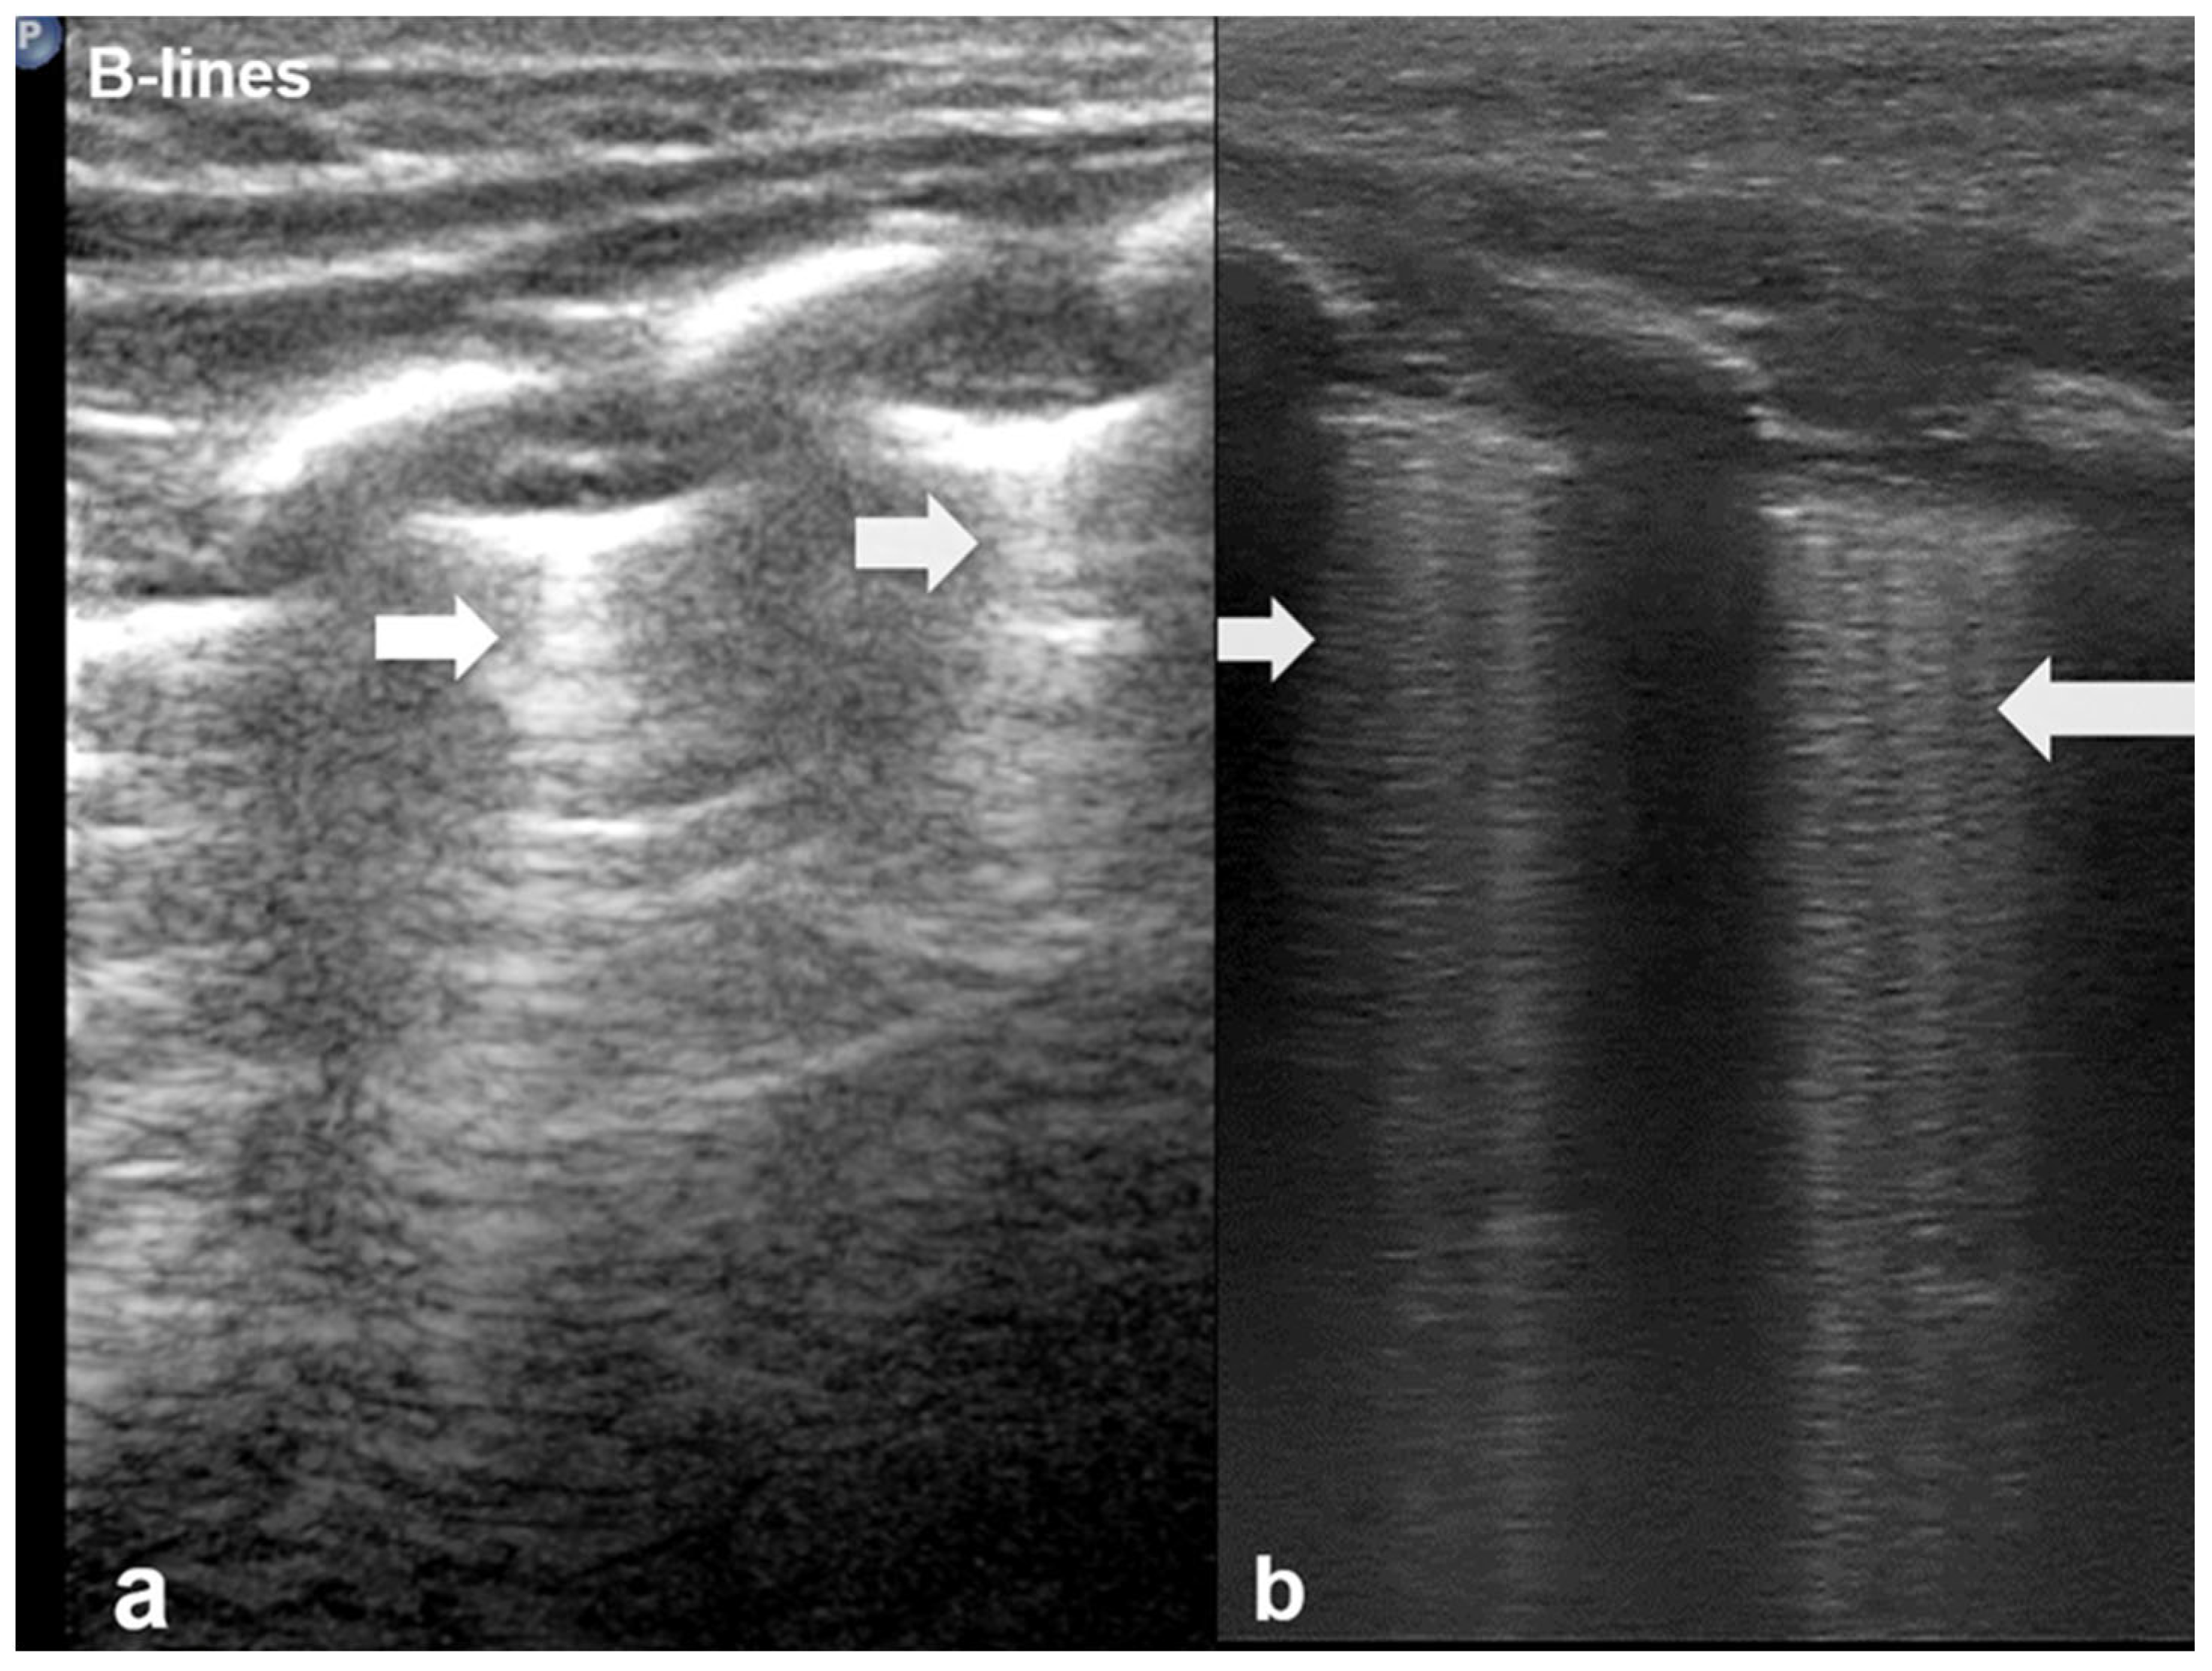

3.1.2. B-Lines